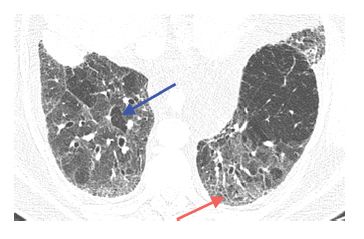

Three principal patterns of reticulation may be seen. These are interlobular septal thickening, honeycombing, and irregular reticulation.

Why is the interlobular septal thickening?

Irregular interlobular septal thickening usually reflects lung fibrosis and is similar in significance to irregular reticulation, which is described later. The architectural distortion associated with fibrosis causes the septa to become jagged or angulated in appearance (Fig. 2.4C, Table 2.1). Irregular septal thickening may be seen with any cause of fibrotic lung disease, and other findings, such as honeycombing and traction bronchiectasis, are more helpful in the formulation of a differential diagnosis.

2.2). Intralobular interstitial thickeningresults in an irregular reticular pattern smaller in scale than the reticular pattern of interlobular septal thickening.

They comprise connective tissue and contain pulmonary veins and lymphatics. Interlobular septa are approximately 1 to 2 cm in length and 1/10th of a millimeter in thickness. Only a few interlobular septa are seen on HRCT in normal patients.

How big is a cyst?

2. Most cysts are 3 to 10 mm in diameter. Some may be larger or smaller.

Is thickening of the interlobular septa a diagnosis?

The presence of a few thickened interlobular septa can be seen in a wide variety of diffuse lung diseases and is, in general, a nonspecific finding. For the purposes of differential diagnosis, thickened septa should be ignored unless they represent a predominant abnormality (Fig. 2.3A, B).